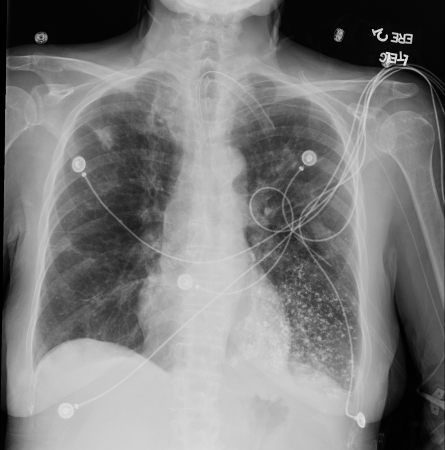

Aspiração de bário. Foi realizada uma esofagografia baritada em uma mulher de 53 anos. Os exames de imagem revelaram material hiperdenso centrado nas vias aéreas no lobo inferior esquerdo, consistente com bronquiolite por aspiração de bário. Foi confirmada uma fístula traqueoesofágica

Da coleção do Dr Augustine Lee; usado com permissão da Mayo Foundation for Medical Education and Research, todos os direitos reservados